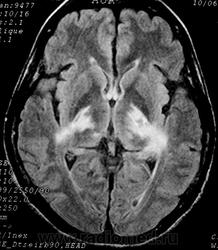

ГМ. Рассеянный склероз 2. +

Рассеянный склероз